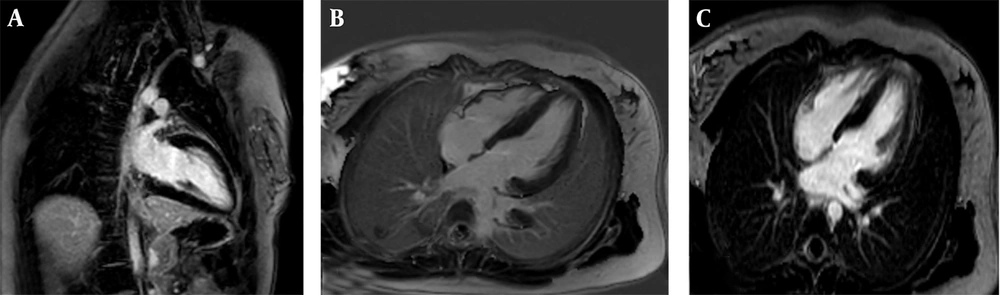

The second case involved an 8-year-old male (height: 120 cm, weight: 25 kg, BSA: 0.92 m2) with symptoms of ataxia, mild speech disorder, and a relevant family history, having a sister (case 1) with similar manifestations. The cardiac MRI protocol was identical, encompassing SSFP cine, LGE, and mapping sequences. Imaging identified mild LV enlargement with concentric LVH, exhibiting a maximum mid-inferoseptal wall thickness of 21 mm. Functionally, there was mildly reduced LV systolic function (LVEF = 46%, EDVI = 105 mL/m2) but normal RV size and function (RVEF = 60%); the LV Mass Index was 115 g/m2. Tissue characterization via LGE revealed diffuse patchy myocardial fibrosis in multiple segments (Figure 2). Collectively, the pronounced LVH, presence of patchy fibrosis, and the neurologic profile confirmed the diagnosis of cardiac involvement in FA.

Cardiac magnetic resonance (CMR) of an 8-year-old male with Friedreich’s ataxia (FA): A, Short-axis cine balanced steady-state free precession (SSFP) image demonstrating concentric left ventricular hypertrophy (LVH) (maximum thickness:21mm) with relatively preserved cavity size; B, Short-axis Magnitude LGE image showing patchy mid-wall enhancement involving multiple myocardial segments consistent with diffuse myocardial fibrosis (arrows); C, Short axis phase sensitive inversion recovery (PSIR) late gadolinium enhancement (LGE) image revealing patchy mid-wall enhancement (arrows) involving multiple myocardial segments, consistent with diffuse myocardial fibrosis.